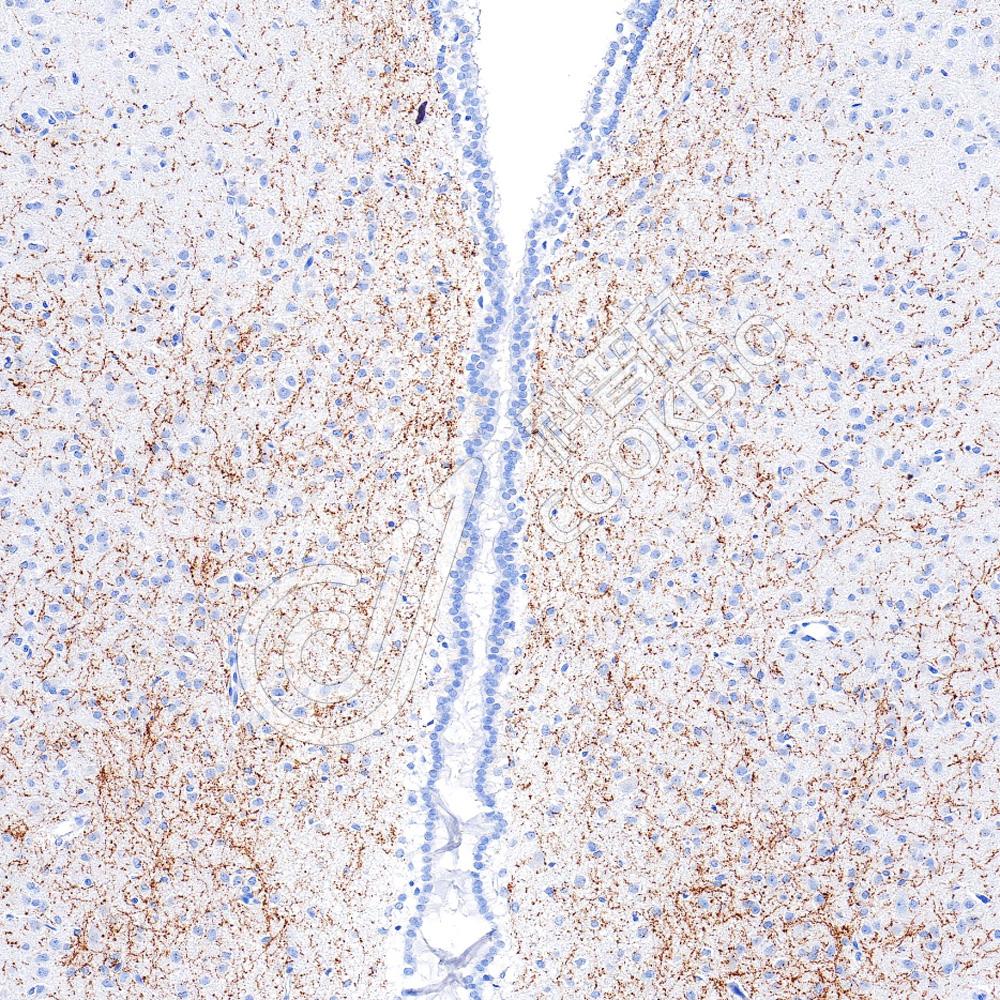

IHC检测AGRP蛋白(货号 K5450414).

样品: 小鼠脑, 4%多聚甲醛 (货号KSG1101) 固定12-24小时.

抗原修复: Tris-EDTA抗原修复液(pH 9.0) (货号KSG1203), 水浴100℃, 25分钟.

—抗: 1: 800稀释, 4℃ 孵育过夜.

二抗: S-vision免疫组化多聚二抗(山羊抗兔),即用型 (货号KB3906), 室温孵育20分钟.

样品: 大鼠脑, 4%多聚甲醛 (货号KSG1101) 固定12-24小时.